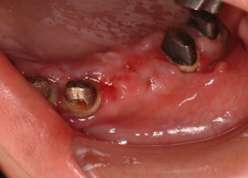

インプラントは歯茎の中の骨がないと植立できません。そのため、その骨が足りない場合が一番、インプラントをする上で問題となります。下顎では過下顎神経管という太い神経が顎の骨の中に通っていますので歯茎からその神経が近い場合骨移植が必要となります。また、上顎では太い神経はありませんが、副鼻腔という大きな空洞が顎の中にありますので、歯茎から副鼻腔が近い場合も骨移植が必要となります。

骨移植はインプラント埋入より、高度な技術が必要ですのでなるべくこの処置をしなくて済むように考案されたのがオールオン4などのコンセプトです。しかし、オールオン4ができないくらい骨がたりない場合などには行います。